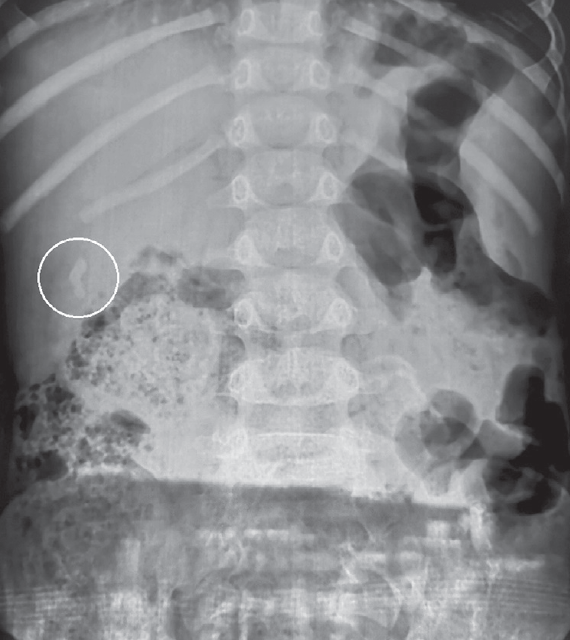

Research result. All patients with cholelithiasis identified different ways deformation in the area of gallbladder duct. One of the major causes of cholelithiasis in children are changes in the gallbladder duct. No patient has ever been found in concretions extrahepatic biliary passages. In patients with chronic stone-free cholecystitis pathology in the area of bladder flow was not found.